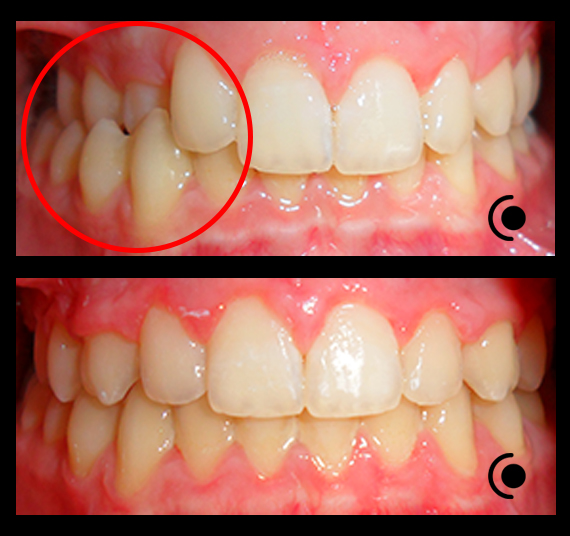

O našoj kvaliteti najbolje govore naši rezultati!

Centar za ortodonciju Petra Džapo